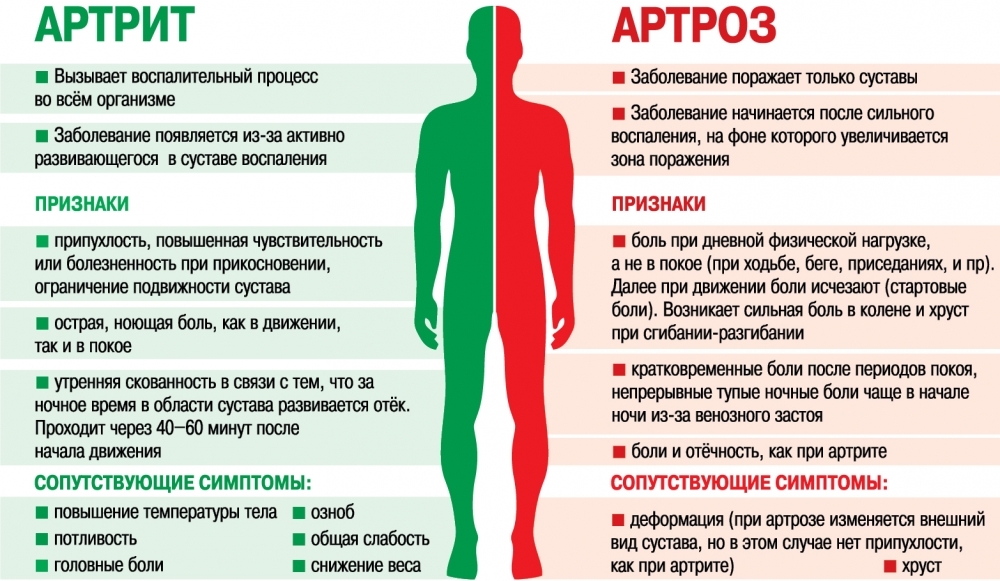

Нередко термины артроз и артрит путают, а также называют артрозо-артритом. Но эти термины имеют принципиально разное значение и разные заболевания. Объединяет их корень(artron) — означающий сустав. Артрит это воспалительное заболевание сустава (суставов) и воспалительный процесс, так или иначе, воздействует на другие органы и системы всего организма вследствие аутоиммунных (например, ревматологические заболевания, такие как ревматоидный артрит, СКВ) или других нарушений. При обменных нарушениях (например, при подагре или сахарном диабете) поражаются суставы и, в таких случаях применяется термин артропатия. Термин артралгия используется для обозначения болей в суставах различного генеза. Артрозы же или остеоартрозы обозначают дегенеративные изменения в суставах, возникающие в возрасте старше 45-50 лет вследствие естественного износа. Таким образом, принципиальной разницей между артритом и артрозом является то, что артрит воспалительное заболевание, в то время как артроз это дегенеративные изменения в хряще вследствие инволюционных изменений в организме и естественного износа хрящевой ткани суставов.

- Артрит это воспаление одного или нескольких суставов.

- Симптомы артрита включают боль и ограничение функции суставов.

Болезнь часто сопровождается болью в суставах (артралгия). Существует много различных причин развития воспалительного процесса в суставах. Это могут быть травмы (остеоартрит), метаболические нарушения (например, подагра или псевдоподагра), наследственные факторы, прямое и косвенное влияние инфекций (бактериальных или вирусных), нарушения в иммунной системе с аутоиммунным компонентом (например, при ревматоидном артрите и системной красной волчанке). Общими для всех видов артритов являются то, что происходит поражение как суставов, так и сухожилий, мышц связок, хрящей и часто поражаются внутренние органы. При некоторых видах артритов, особенного аутоиммунного генеза, поражаются внутренние органы (сердце, легкие, почки) и у пациента могут быть симптомы общего характера, такие как повышение температуры, хроническая усталость, потеря веса, увеличение лимфоузлов.

Симптомы артрита включают боль и ограничение подвижности в суставах. Воспаление суставов характеризуется скованностью, отечностью, покраснением и местным увеличением температуры в области сустава. Также может отмечаться болезненность в области сустава. При многих типах артритов возникает симптоматика со стороны других органов, напрямую не связанных с суставами. Таким образом, у пациентов с артритом могут быть такие симптомы, как повышение температуры увеличение лимфоузлов,потеря веса и симптомы нарушения функций таких органов, как легкие, сердце или почки.

Симптомы развиваются очень медленно. На ранней стадии эрозии хряща симптомов может не быть. Кроме того, артроз является дегенеративным заболеванием, а не воспалительным состоянием и поэтому может не проявляться в течение длительного времени. После начала появления симптомов состояние постепенно ухудшается также в течение длительного периода времени. Ведущим симптомом при артрозе является боль.

Ведущим симптомом при артрозе является боль.

Боль, как правило, изолированная в пораженном суставе. Боль обычно усиливается во время и после движения в пораженном суставе. В более легких случаях боль не появляется во время движения, а лишь некоторое время спустя после нагрузки. Возможно также наличие болезненности при пальпации в области сустава. Но болезненность при артрозе обычно не сопровождается отеком, как это бывает при воспалительных явлениях в суставе (например, при ревматоидном артрите).

Скованность сустава является еще одним распространенным симптомом. Это наиболее заметно при пробуждении утром и после длительного периода покоя. Движение может снизить скованность, но чрезмерное движение в конечном итоге приведет к боли. Скованность в суставе имеет тенденцию к ухудшению с течением времени, по мере прогрессирования заболевания. Даже тогда, когда скованность в суставе уменьшается, нормальный диапазон движения не восстанавливается. Со временем это приводит к значительному снижению двигательной активности. В суставе может также появиться хруст при движении, особенно по мере прогрессирования болезни. Обычно суставные хрящи на концах костей трутся друг о друга, но в связи с гладкой поверхностью и хорошей смазкой синовиальной жидкостью это трение не приводит к появлению звуков. При артрозе же хрящевая поверхность не такая гладкая и это приводит к появлению звуков при движении в суставе (хрусту, скрежету). Уплотнение – крупные суставы, такие как коленные становятся более плотными на ощупь. Костные разрастания, возникающие при артрозе (остеофиты), образуются в течение времени и могут прощупываться под кожей в виде

Артрит — это общий термин, относящийся к воспалению суставов. Но не все артриты одинаковы — между остеоартритом и ревматоидным артритом есть существенные различия. ОА — это дегенеративное заболевание, поражающее в основном пожилых людей, в то время как РА чаще всего встречается в среднем возрасте. Боль в суставах при ОА часто возникает только с одной стороны, например, в правом колене или левой руке, в то время как боль в суставах при РА обычно симметрична.

Несмотря на то, что и остеоартрит, и ревматоидный артрит сопровождаются некоторыми сходными симптомами, такими как тугоподвижность суставов и воспаление, существуют и другие признаки, связанные с ревматоидным артритом. Поскольку ревматоидный артрит является аутоиммунным заболеванием, оно влияет не только на суставы, но и на симптомы со стороны тела, и часто сопровождается субфебрилитетом, снижением аппетита и усталостью.